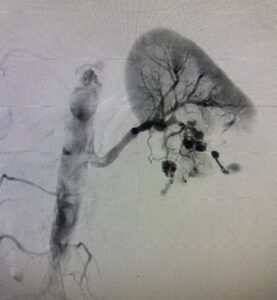

这家医院的急救IVR组正广泛地和急性失血以及栓塞,血管闭塞等的紧急的疾病不仅外伤而且用体制24小时365天对应。灵活地运用动脉栓塞术(TAE)以及以血管内帐篷拘留方法代表的最尖端的IVR技术,用传统的外科手术提供也对救命困难的症例低速作为侵袭的治疗。

生存率用Hybrid ER×IVR×外科的联合提高

在这家医院,灵活运用Hybrid ER,实施密切地和急救科、外科组合作的Hybrid手术。外伤以及消化管出血,严重急性胰腺严CT诊断之后不久针对需要紧急对应的症例开始IVR治疗,是什么外科手术和组合的混合根据情况接近,并且正飞跃地提高救命率。

✅ 马上被CT诊断以后在Hybrid ER提高IVR开始,出自时间缩短的救命比率